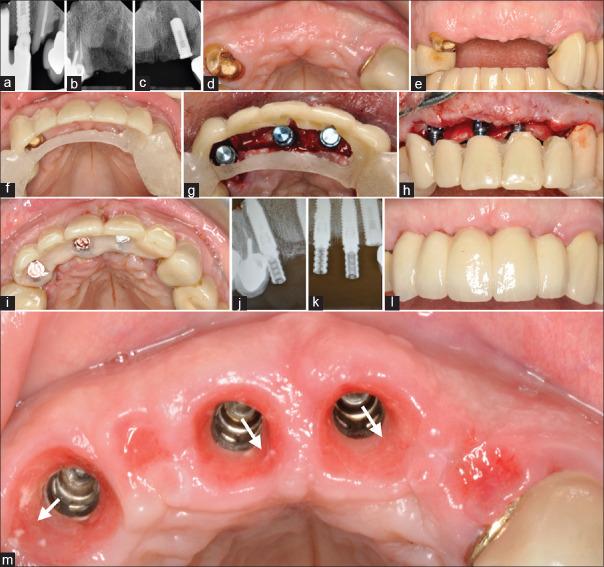

The long-term safety of xenografts and their potential association with disease are valid concerns. Bovine bone substitutes which are by far the most commonly used xenografts in dentistry are not biodegradable. The aim of the present report was to raise awareness on the long-term risks of the bovine-derived xenografts. Patients who experienced clinical complications after xenografting are reported. Patients' demographic, significant medical, and dental findings are reported. Complications included migration/encapsulation/displacement of the graft material, chronic inflammation, and soft-tissue disturbances/fenestrations. Albeit some xenograft complications are not significant enough to compromise the initial outcomes achieved, the xenografted particles seemed to be left intact favoring conditions for migration. The authors observed the inability of the human host to biodegrade the xenograft particles. The intact/migrated bovine bone particles present a risk to patients and may contribute to long-term clinical complications in implant dentistry.